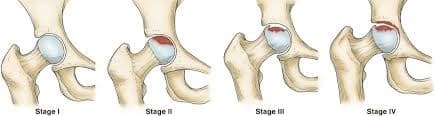

Өвчний аль үе шатанд мэс засал эмчилгээг санал болгох вэ

Остеоартрит

Остеоартрит нь ихэвчлэн 50 болон түүнээс дээш насныханд үений мөгөөрсөн эдийн тэжээл, уян чанар , алдагдсанаар үүсдэг өвчин юм. Мөгөөрсөн эдийн гөлгөр гулсамтгай шинж чанар алдагдаж, өвчин даамжирсаар үе хоорондын мөгөөрсөн эдийн бүтэц алдагдан үгүй болж , үе үүсгэж буй яснууд хоорондоо үрэлцэх энэ тохиолдолд хүчтэй өвдөлт үүсдэг. Зарим судлаачид энэхүү өвчнийг удамшилтай холбоотой ч гэж үздэг. Мөн биеийн жингийн илүүдэл, гэмтэл бэртэл, төрөлхийн үений эмгэг, тэнхлэгийн гажиг нь остеоартрит өвчин үүсэхэд нөлөөлдөг.

Дунд чөмөгний толгойн үхжил

Тодорхой шалтгааны улмаас дунд чөмөгний толгойд очих цусан хангамж алдагдаж, толгойн хэсэг тэжээлгүй болсноор дунд чөмөгний толгой нь үхжилт бүхий өөрчлөлтөнд ордог түгээмэл эмгэг юм.